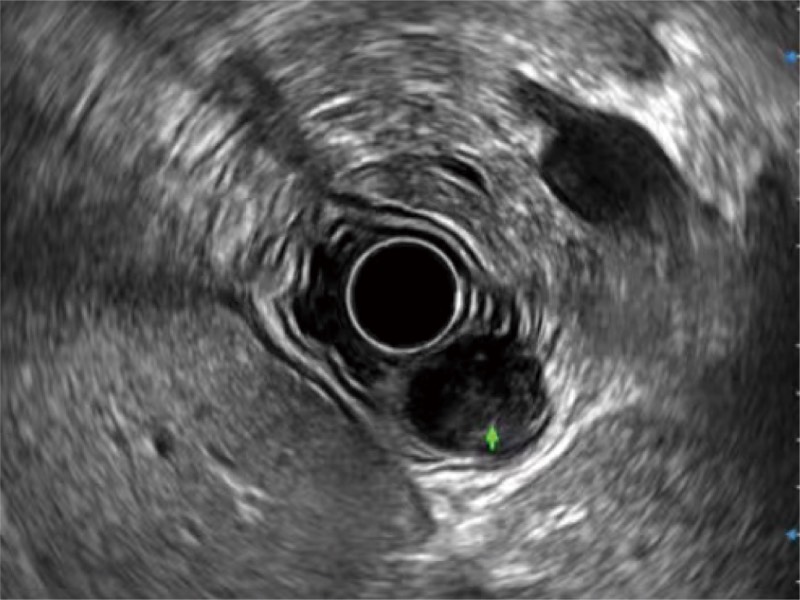

• 食管内间质瘤清晰显像